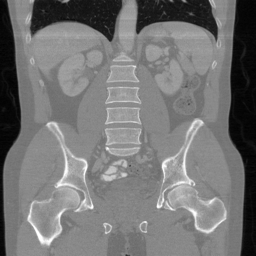

![]() |

| PSNR = dB | PSNR = 12.43 dB | PSNR = 36.20 dB | PSNR = 36.56 dB | PSNR = 37.23 dB |

Main results: In Table 1, we present quantitative results and in Figure 2, we show visualizations in the axial, coronal, and sagittal planes. Our methods consistently outperform the second-best baseline across most views, achieving nearly 1 dB higher PSNR on average. Despite incorporating a few additional input updates to enforce data consistency, our method reaches competitive performance with only 30 sampling steps. Based on the visualizations, we observe that DDS introduces slight artifacts along the horizontal direction, particularly noticeable in the coronal and sagittal views. In contrast, our method produces cleaner reconstructions with fewer artifacts in these orientations.